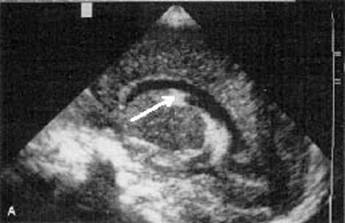

Grade I Subependymal hemorrhage (sagittal view).